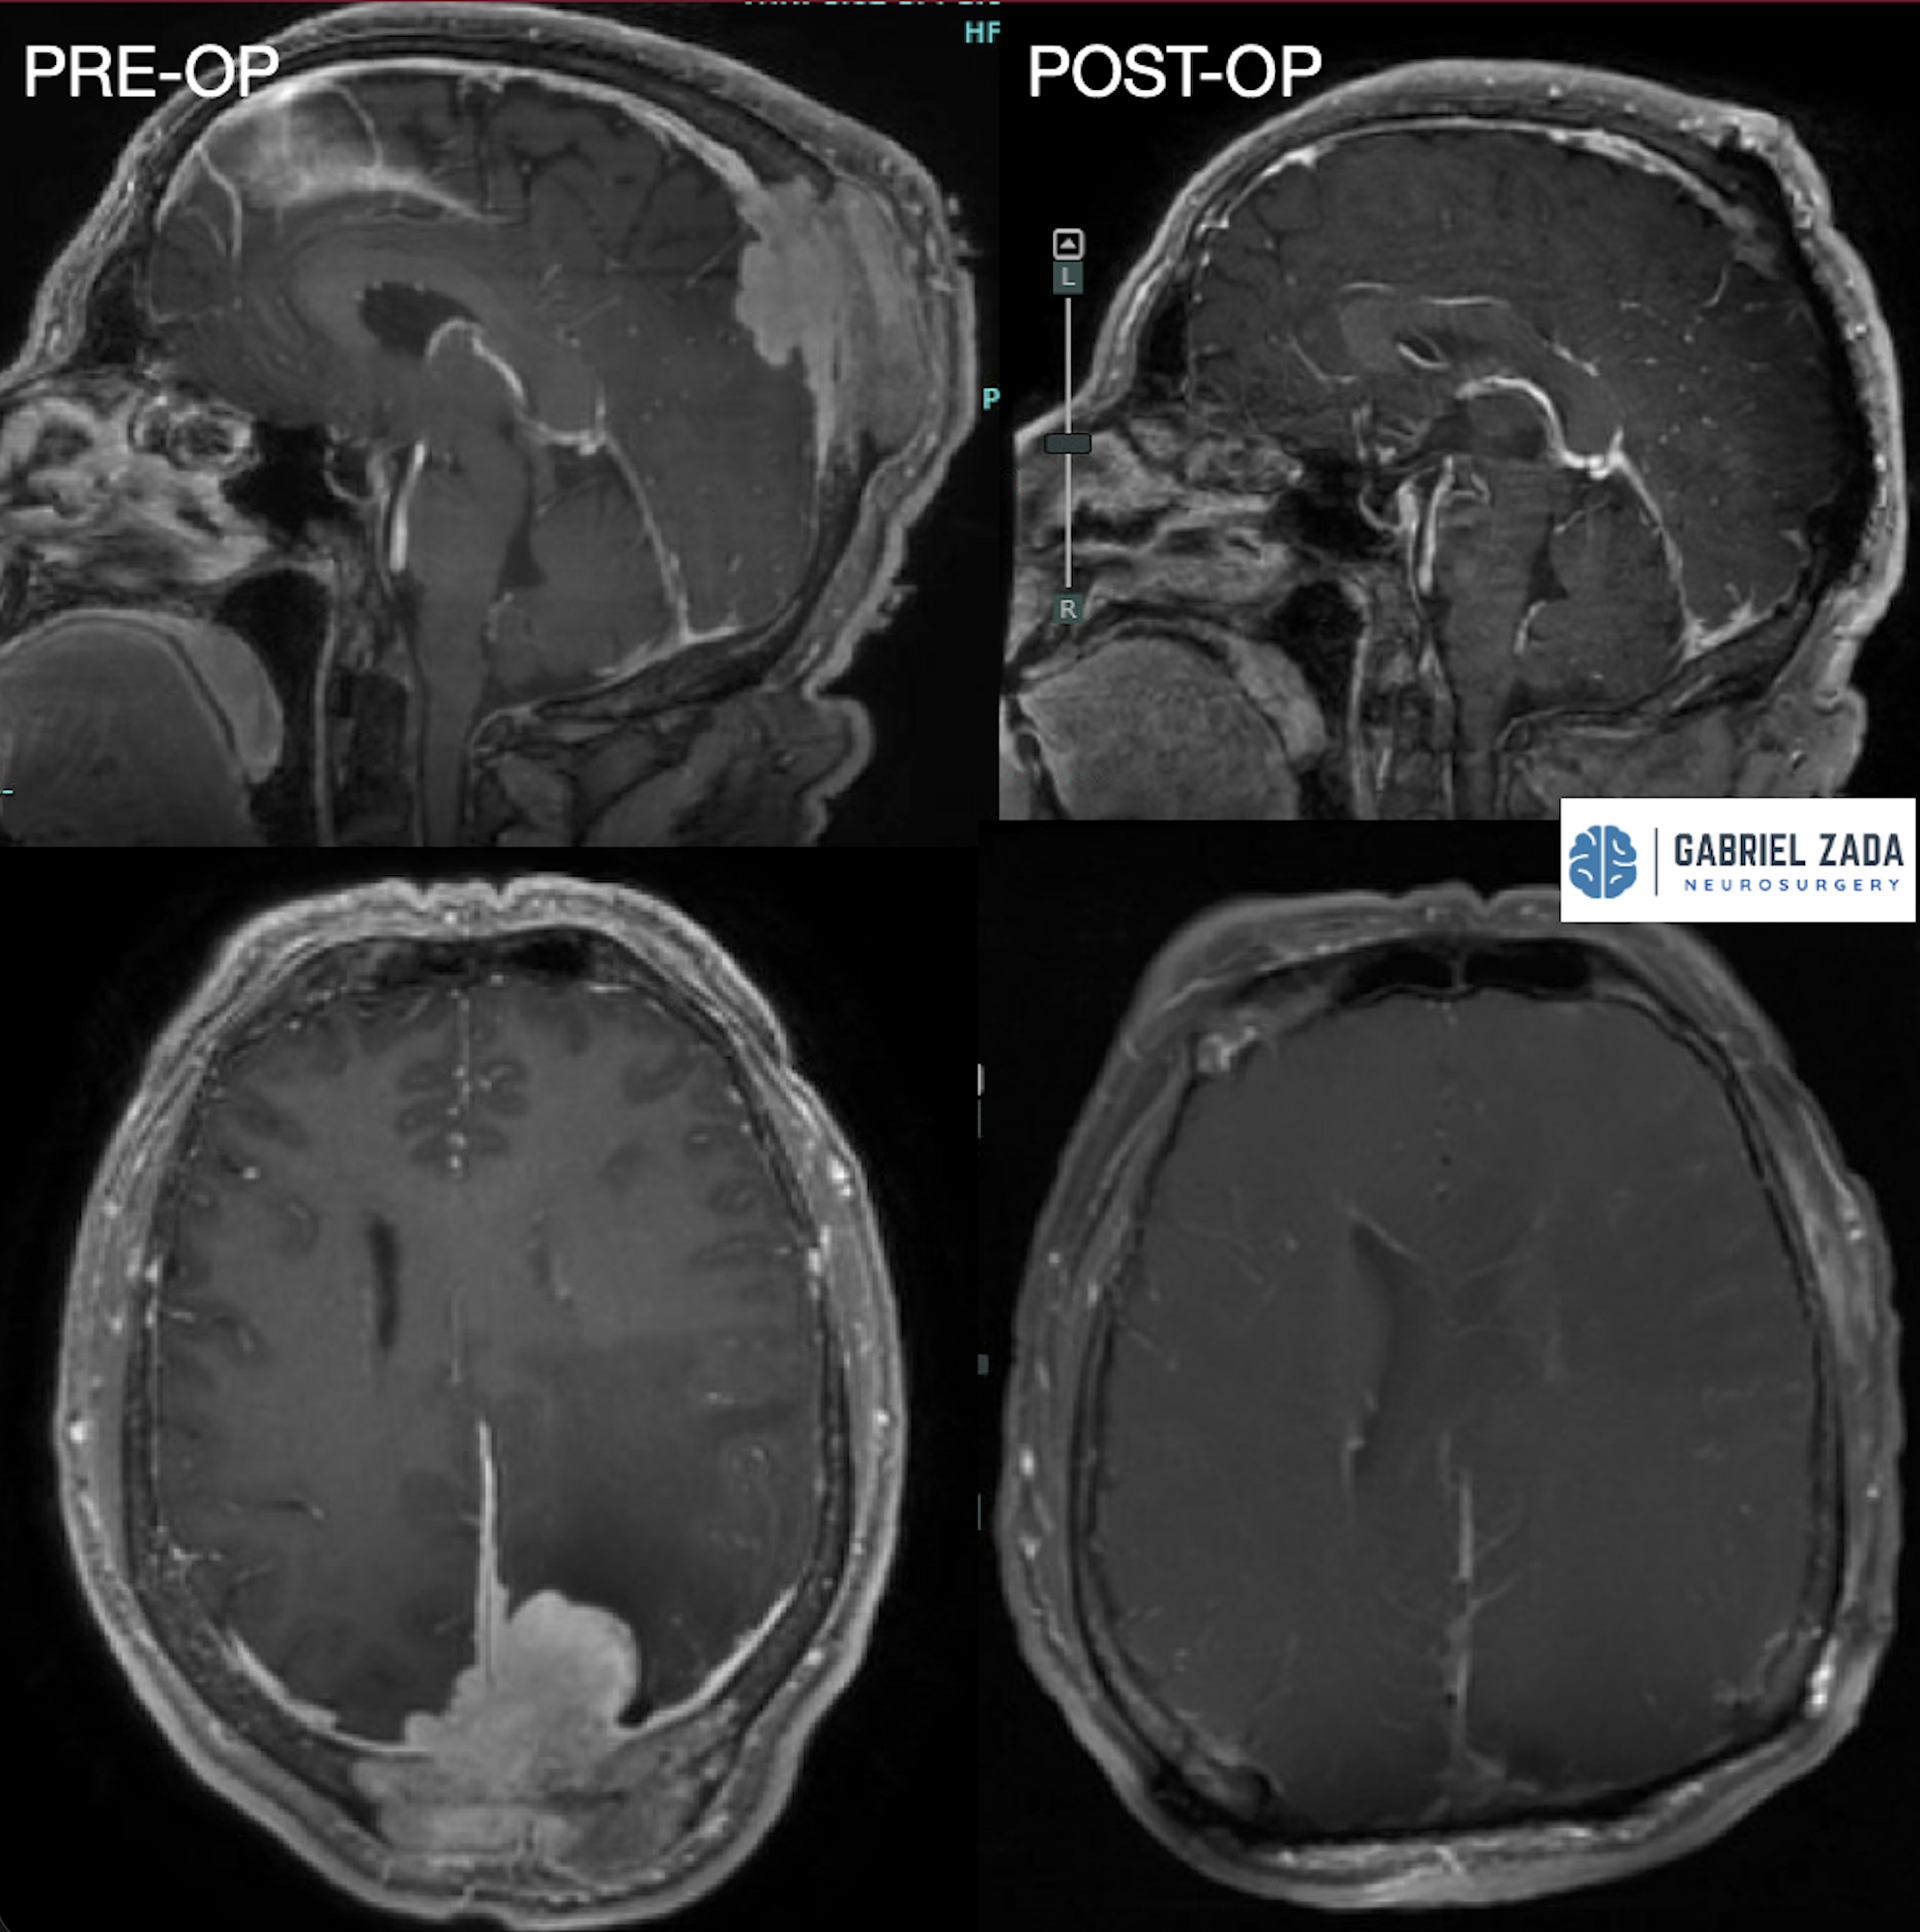

Explore this comprehensive gallery featuring pre‑ and post‑operative imaging of patients with skull‑base tumors treated by Gabriel Zada, MD, MS, FAANS, FACS. These cases highlight Dr. Zada’s expertise in advanced neurosurgical techniques and outcomes.

*Representative cases shown for educational purposes. All images de-identified. Individual results vary.